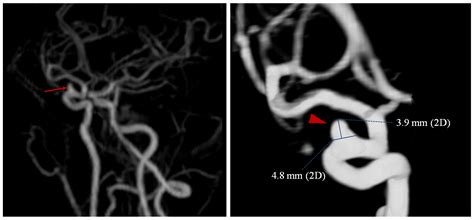

An angiogram of the brain, also known as a cerebral angiogram, is a type of X-ray test that uses a special dye and camera (fluoroscopy) to take pictures of the blood vessels in the brain. This procedure helps doctors identify blockages, narrowing, or abnormalities in the blood vessels that could lead to strokes or other neurological issues.